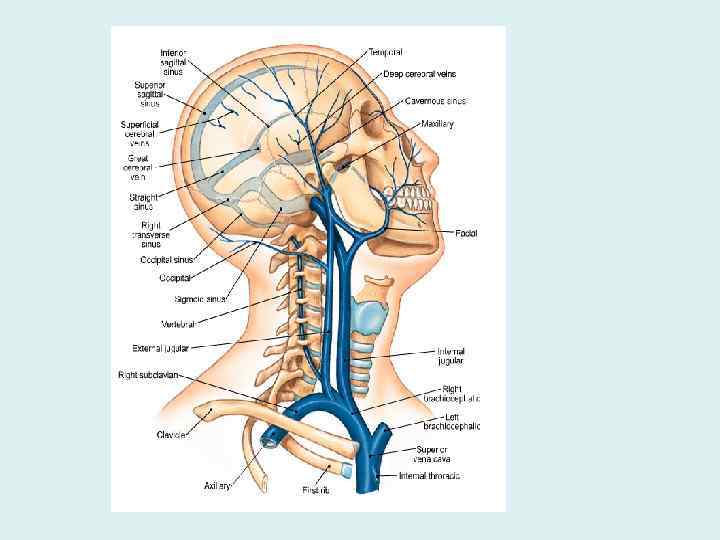

Внутренняя яремная вена • Собирает кровь от головы и шеи, из бассейна наружной и внутренней сонных и позвоночных артерий • Исток: сигмовидный синус • Притоки: внутричерепные и внечерепные

Внутричерепные притоки • • • Синусы твердой мозговой оболочки диплоические вены, глазные вены, вены лабиринта, мозговые вены, вены оболочек

Синусы твердой мозговой оболочки

Синусы твердой мозговой оболочки • Стенки синусов сращены с твердой оболочкой, • не спадаются, • обеспечивают свободный отток крови от мозга • Это вены волокнистого типа

Внечерепные притоки • • • Лицевая вена Позадичелюстная вена Глоточные вены Язычная вена Верхние щитовидные вены Средняя щитовидная вена

Анастомозы внутричерепных и внечерепных притоков • Вены выпускники, диплоические вены соединяют синусы с венами свода черепа • Крыловидное сплетение соединяет средние оболочечные вены с позадичелюстной и лицевой венами

Анастомозы внутричерепных и внечерепных притоков • Глазная вена соединяет пещеристый синус с лицевой веной